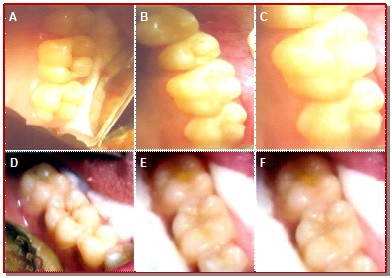

The present study compared the clinical performance of nanoparticulated resin modified glass ionomer and conventional glass ionomer pit and fissure sealant on permanent molars. Fifty patient having bilateral occlusal grooves in pits and fissures of the occlusal surface were included for this study where 50 teeth were treated with nanopaticulated resin modified and the remaining 50 teeth were subjected to conventional glass ionomer sealants. The color match, retention and marginal adaptation were assessed at 3, 6 and 12 months and statistical analysis was performed by Chi-square test to assess the difference between the two sealants; a values of <0.05 was considered as statistically significant. The results showed that although there were no significant differences between two sealants at baseline and 3 months observation period but nanoparticulated resin modified glass ionomer sealants showed better clinical performance than that of conventional glass ionomer sealants at 12 months and the differences between two sealants were statistically significant (p<0.05). It can be concluded that naqnoparticulated resin modified glass ionomer sealant exhibited better color stability, more retention, and better marginal adaptation than those of conventional glass ionomer sealants at 12 months observation period.